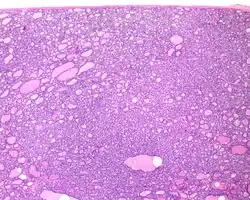

1) Encapsulated or partially encapsulated. The tumors are usually very well delimited or circumscribed, with the majority encapsulated, surrounded by a well formed fibrous connective tissue capsule.

3) Predominantly follicular pattern of growth. Papillary structures should not be present. Further, solid, insular, or trabecular architecture must be <30% of the overall tumor for this category to still apply. Colloid (the material that thyroid follicular cells create) is easily identified throughout.

Definition of noninvasive follicular thyroid neoplasm with papillary-like nuclear features (NIFTP): A noninvasive neoplasm that arises from the thyroid follicular cells (cells that normally make thyroid hormone), showing a predominantly follicular growth pattern and with nuclear features of papillary thyroid carcinoma. There are several specific inclusion and exclusion criteria (see below). When these are met, this tumor has an extremely low malignant potential.[3]